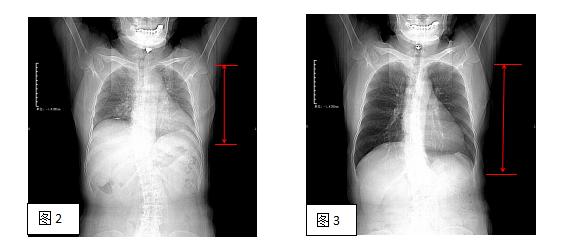

那么之所以要憋气是因为呼吸时膈肌上下移动,从而引起肺部和腹部器官上下移动。(如图 2、3)